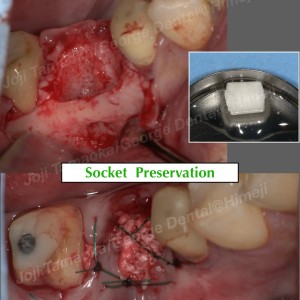

▶︎ デジタル技術による安全なインプラント手術

当院では、インプラント治療はすべて

🖥 デジタルシミュレーション + サージカルガイド

を使用しています。

• CTデータと口腔内スキャンを合成

• インプラントの最適ポジションを事前にミリ単位で設計

• 設計通りに正確に埋入できるガイドを作製

これにより手術の安全性が高まり、

神経損傷などのリスクを最小限に抑えた“予測性の高い治療”が可能となります。

今回もガイドを用いることで、短時間で正確な埋入が実現しました。

② デジタルガイドを用いた正確なインプラント手術

→ 神経や周囲組織へのリスクが低い

・ガイドサージェリー(安全に埋入するためのコンピュータガイド) 60,000円